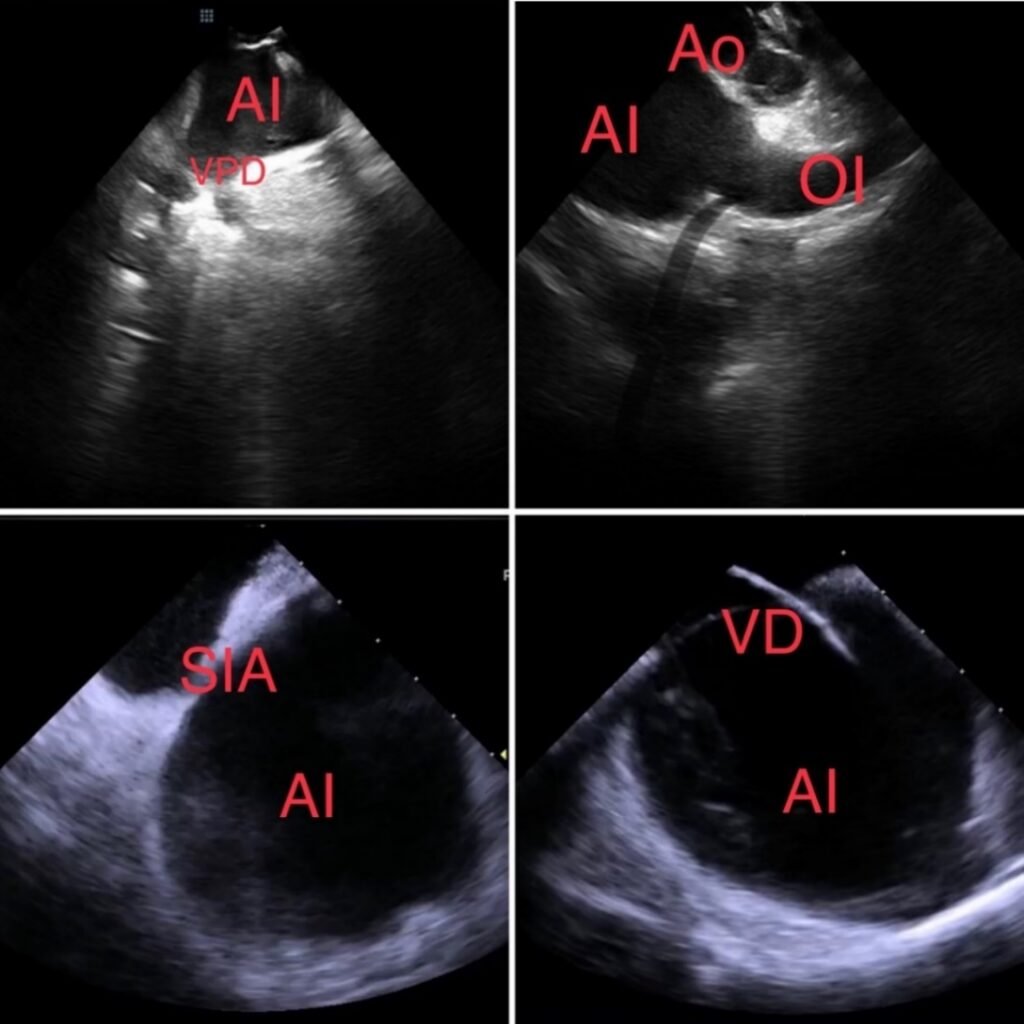

Cierre Percutaneo de Orejuela Izquierda

El procedimiento de Cierre de la Orejuela Izquierda es un tratamiento diseñado para reducir el riesgo de accidente cerebrovascular (ACV) en pacientes con Fibrilación Auricular (FA).

- ¿Qué es la Orejuela? Es un pequeño saco o apéndice muscular ubicado en la parte superior izquierda del corazón (la aurícula izquierda). Es una cavidad que no es esencial para la función normal del corazón.

- El Riesgo en FA: La Fibrilación Auricular es un latido irregular que hace que la sangre se «estanque» y se mueva lentamente dentro del corazón. Los estudios demuestran que, en pacientes con FA, alrededor del 90% de los coágulos de sangre que causan ACV se forman precisamente dentro de esta Orejuela.

- El Objetivo: El procedimiento busca sellar o cerrar la Orejuela para impedir que los coágulos que se formen allí puedan salir y viajar al cerebro.

La forma más común de realizar este cierre es mediante un procedimiento mínimamente invasivo:

Se realiza bajo anestesia general.

Se hace una pequeña punción (similar a un cateterismo) en una vena de la ingle (pierna).

Se introduce un catéter a través de la vena hasta llegar al corazón y la Orejuela Izquierda. A través del catéter, se despliega un dispositivo de cierre (que parece un pequeño paraguas o tapón) dentro de la Orejuela. Este dispositivo sella permanentemente la abertura de la Orejuela.